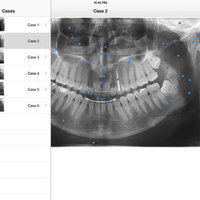

iPanoramic

The app provides dental students and dental hygiene an easy and fun way to master different anatomical landmarks. Dental practitioners can use the app to refresh their knowledge about panoramic radiographs. The app can be used a quick reference when needed. It's fully interactive and allows knowledge assessment through a quiz mode.